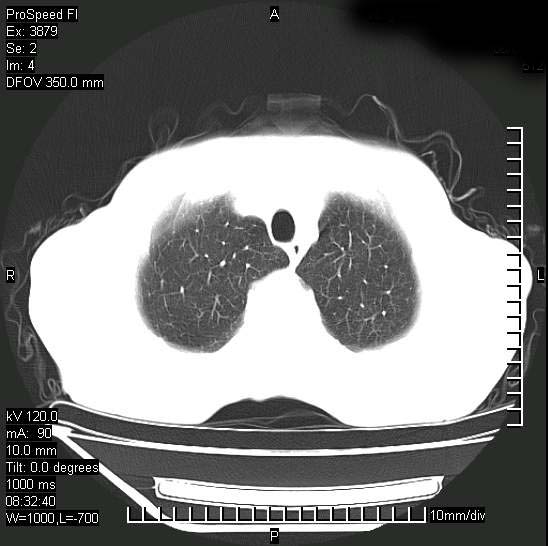

以下是引用37度在2008-6-6 11:20:00的发言:[br]1.包裹性积液,多考虑结核性;[br]2.穿刺术后改变。

以下是引用312nanyang在2008-6-6 15:12:00的发言:[br]基本支持楼主意见[br]疑问?左下肺支气管旁的软组织(16层)密度怎么解释?淋巴结还是斜裂胸膜增厚所致?能否增强进一步检查